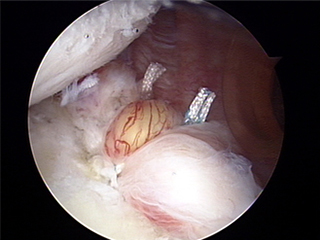

2. 수술은 관절경 수술로 대부분의 습관성 탈구가 치료 가능하다.

수술 후